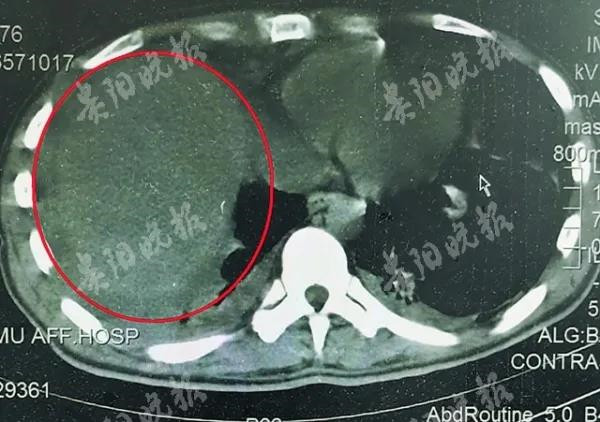

遵義醫科大學附屬醫院急診科劉同英醫生說,羅某顱腦CT右側顳頂葉腦出血、右側顳頂葉腦水腫,左側肺少量液氣胸、右側肺有少量胸腔積液。此外,他的肝右葉也受到了損傷。

羅某被寄生蟲入侵的肝臟